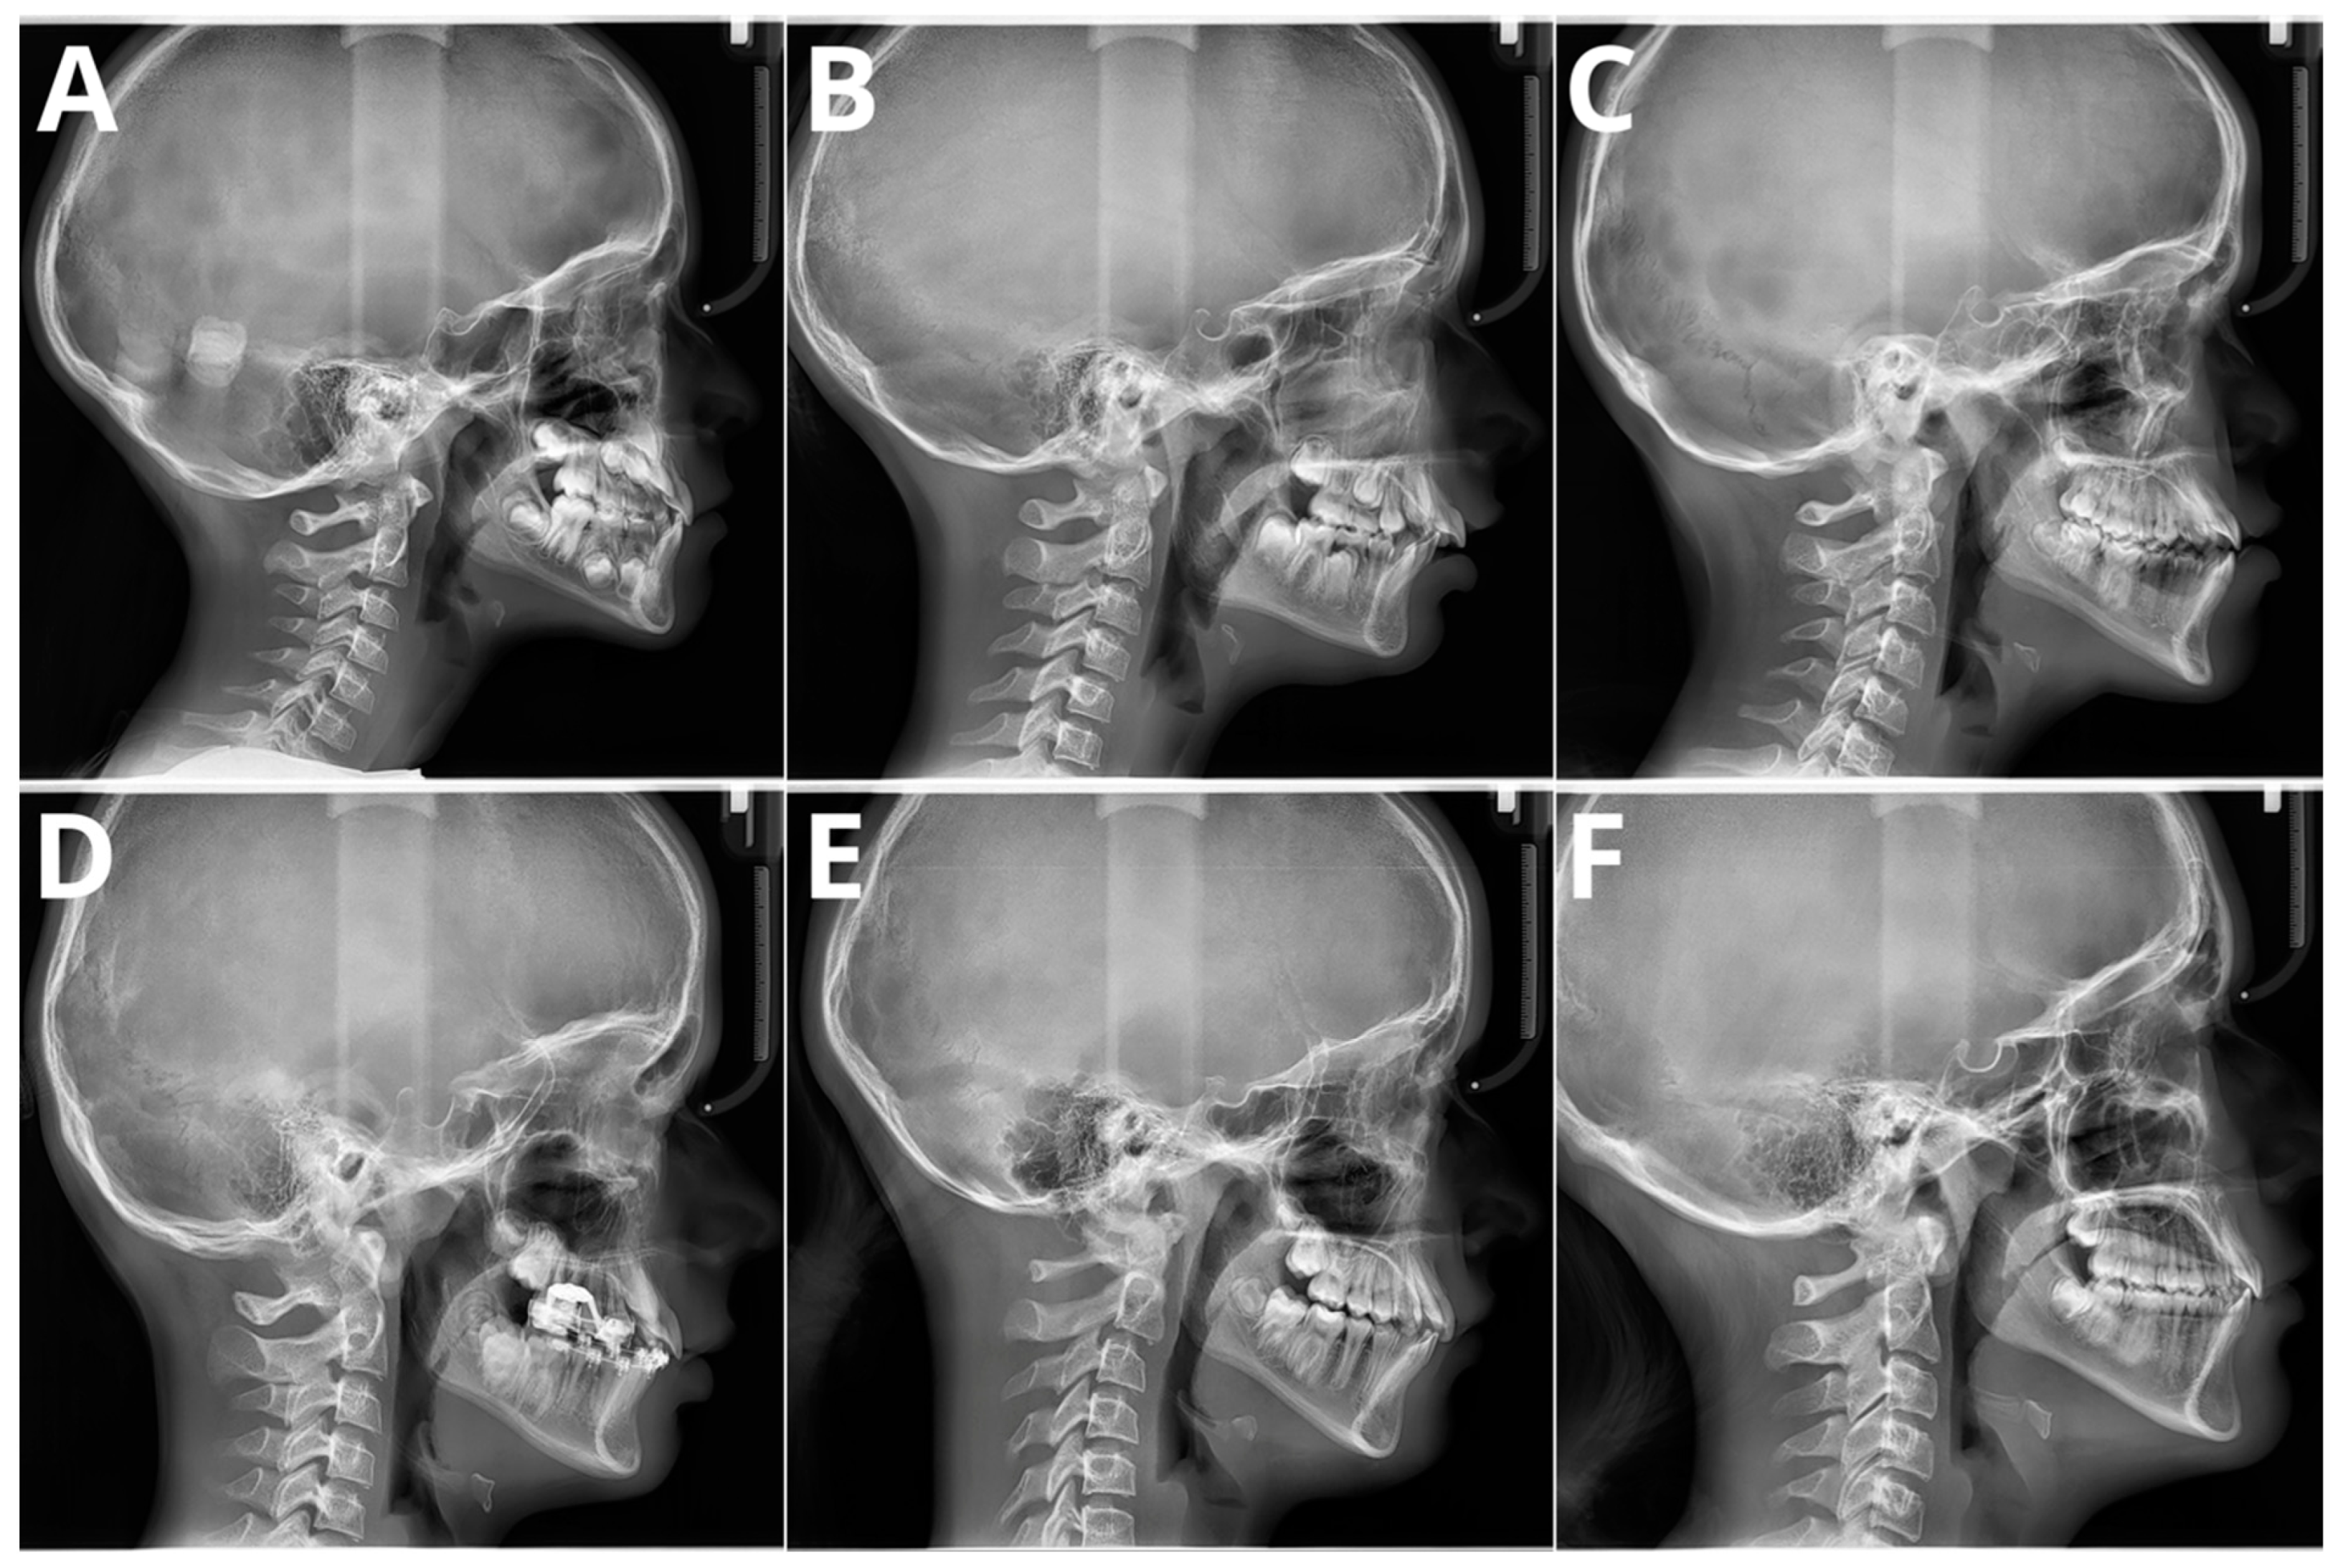

The significant problem associated with CVM evaluation is high inter- and intra-rater variability. A recent paper by Shoretsaniti et al. [] evaluated the reproducibility and efficiency of CVM assessment. The study included evaluations by six experts in radiology and orthodontics. The intra-rater reliability ranged from 77.0% to 87.3%, meaning that up to 1/4 of the diagnoses of CVM stage were changed. The results of the inter-rater agreement were even worse, with an absolute agreement calculated at 42.8%. The study also showed the lowest reproducibility for stage 3, a crucial stage that marks the beginning of pubertal growth. These results align with other studies that show significant discrepancies in CVM assessment [,,]. Such low scores of both inter- and intra-rater reproducibility indicate that the assessment of CVM stage is biased due to high variability among raters. Therefore, the results of studies showing more than 90% AI accuracy in CVM assessment should be considered very optimistic. It should be emphasized that individual errors and inconsistencies by raters assessing the CVM stage in the training sample significantly impact the learning process of the applied AI model. However, as stated in a Nature paper by Topol [], AI will likely boost human performance and accelerate decision-making in currently problematic tasks. Figure 4 presents samples of all six stages verified according to the method by Bacetti et al. [].

Figure 4.

Six maturation stages according to the method by Bacetti et al. (A) stage 1, 7 years old female; (B) stage 2, 9 years old female; (C) stage 3, 11 years old male; (D) stage 4, 12 years old male; (E) stage 5, 13 years old female; (F) stage 6, 13 years old female. Population of single, private orthodontic center, rater—orthodontist with 11 years of experience.